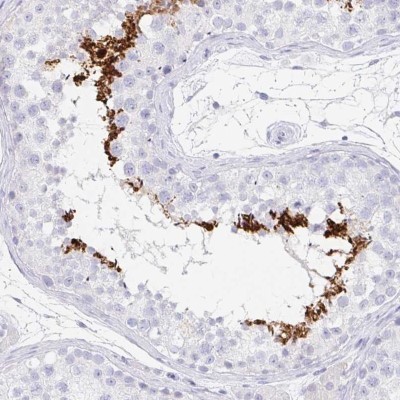

- Immunohistochemistry-Paraffin: C2orf57 Antibody [NBP2-14406] - Staining in human testis and kidney tissues using anti-TEX44 antibody. Corresponding TEX44 RNA-seq data are presented for the same tissues.